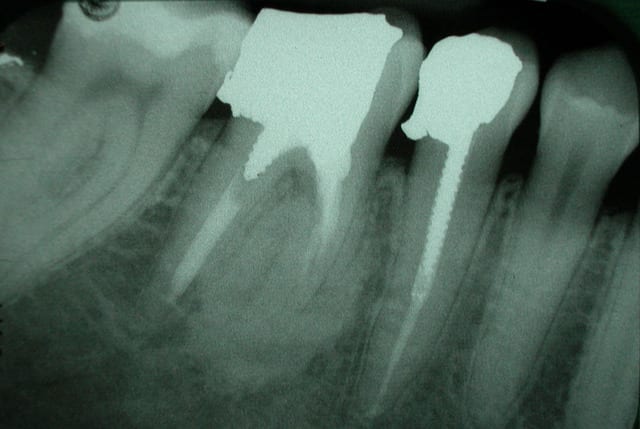

qu'est que cela peut il etre?

dent asymptomatique.

Normal mon chou, rien à faire lésion cemento-osseuse très difficile à classer même pour l'oms

tu peux écarter les fibromes cemento-ossifiant (il manque le halo radio clair périphérique) e n'est pas non plus une dysplasie fibreuse il n'y apas de déplacement de structure dentaire tu peux t'orienter vers une dysplasie céménto-osseuse péri apicale à forme dense quel age? Femme?

c'est^pas méchant, c'est souvent une formation cementoïde corrélable au traitement endo, l'os est fou et ne reconnaît plus les cellules cimentaire...

je ne suis pas endo, mais en temps qu'osseuphile je ne rettt pas pas d'inflammation sup dans ce flou ossifiant et les images en distal de la 7 c'est là depuis longtemps ou c'est de l'amalgame tout frais, fais ta couronne en expliquant la présence de cette image ostéocondensante à la patiente , femme 3 décade correspond bien avec une dysplasie cemento-osseuse terme anapath qui veut dire on s’en fout il ya des cellules cementaire et osseuses en structure malformative résultant d'une anomalie du développement d'un tissu .

dernière interrogation, ce phenomene est il associé à une resorption radiculaire?(qui pourrait comprometre la durée de vie de la dent?)

tres lentement evolutif certe!